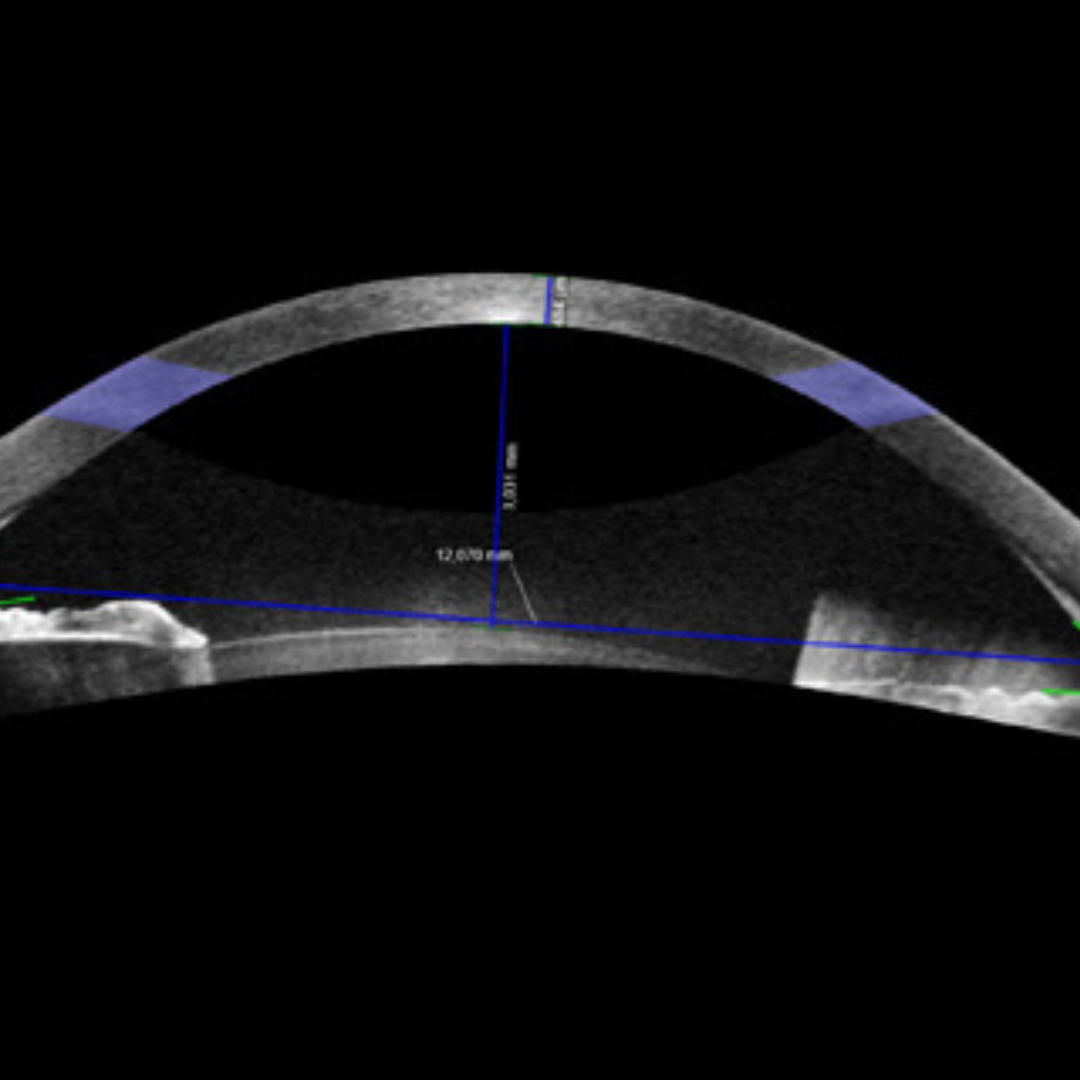

Topografia Corneale

Esame avanzato che analizza in dettaglio la superficie della cornea, fondamentale per identificare patologie come il cheratocono o per personalizzare le lenti a contatto.

Costo: €70 (secondo controllo entro due anni: €40)

Pachimetria Corneale (Spessore Corneale)

Esame che misura lo spessore della cornea. È utile per valutare la reale pressione intraoculare e per identificare condizioni come edema, cheratocono o predisposizione al glaucoma.

Costo: €40